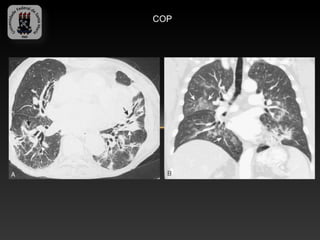

-PNEUMONIA EM ORGANIZAÇÃO

-Proliferação de tecido de granulação dentro dos espaços aéreos

-Pode ser idiopática ou associada a d. do tec. conjuntivo, infecções,

broncoaspiração e drogas.

- Apresenta-se com instalação subaguda de sintomas semelhantes a

gripe.

-Achados TC:

-   Áreas esparças uni ou bilaterais de consolidação

-   Consolidação focal

-   Nódulos pequenos de mal definidos

-   Sinal do halo invertido

COP

DPD 6- Pneumonias intersticiais idiopáticas -PNEUMONIA EM ORGANIZAÇÃO -Proliferação de tecido de granulação dentro dos espaços aéreos -Pode ser idiopática ou associada a d. do tec. conjuntivo, infecções, broncoaspiração e drogas. - Apresenta-se com instalação subaguda de sintomas semelhantes a gripe. -Achados TC: - Áreas esparças uni ou bilaterais de consolidação - Consolidação focal - Nódulos pequenos de mal definidos - Sinal do halo invertido